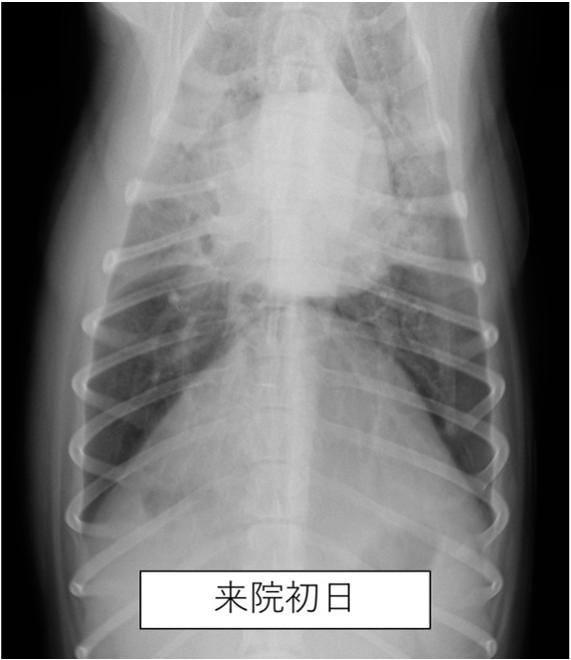

胸部のレントゲン撮影にて肺野全体の不透過性亢進(白く見える部分)が認められた。

| 誤嚥性肺炎とは、唾液や食べ物、胃液、吐物などの異物を吸引してしまうことで生じる肺炎です。加齢などにより気道反射が低下している動物や短頭種(パグやブルドッグなど)で起こりやすいと言われています。 本症例は上記の条件に当てはまりませんが、スポンジをかじる中で細かい粒子を吸い込んでしまった可能性があります。 幸いにも、本症例は抗生物質の投与により2週間ほどでレントゲン画像所見は消失し治療終了となりましたが、場合により致命的な状態まで悪化してしまうこともあります。早期発見・治療が重要です。 |